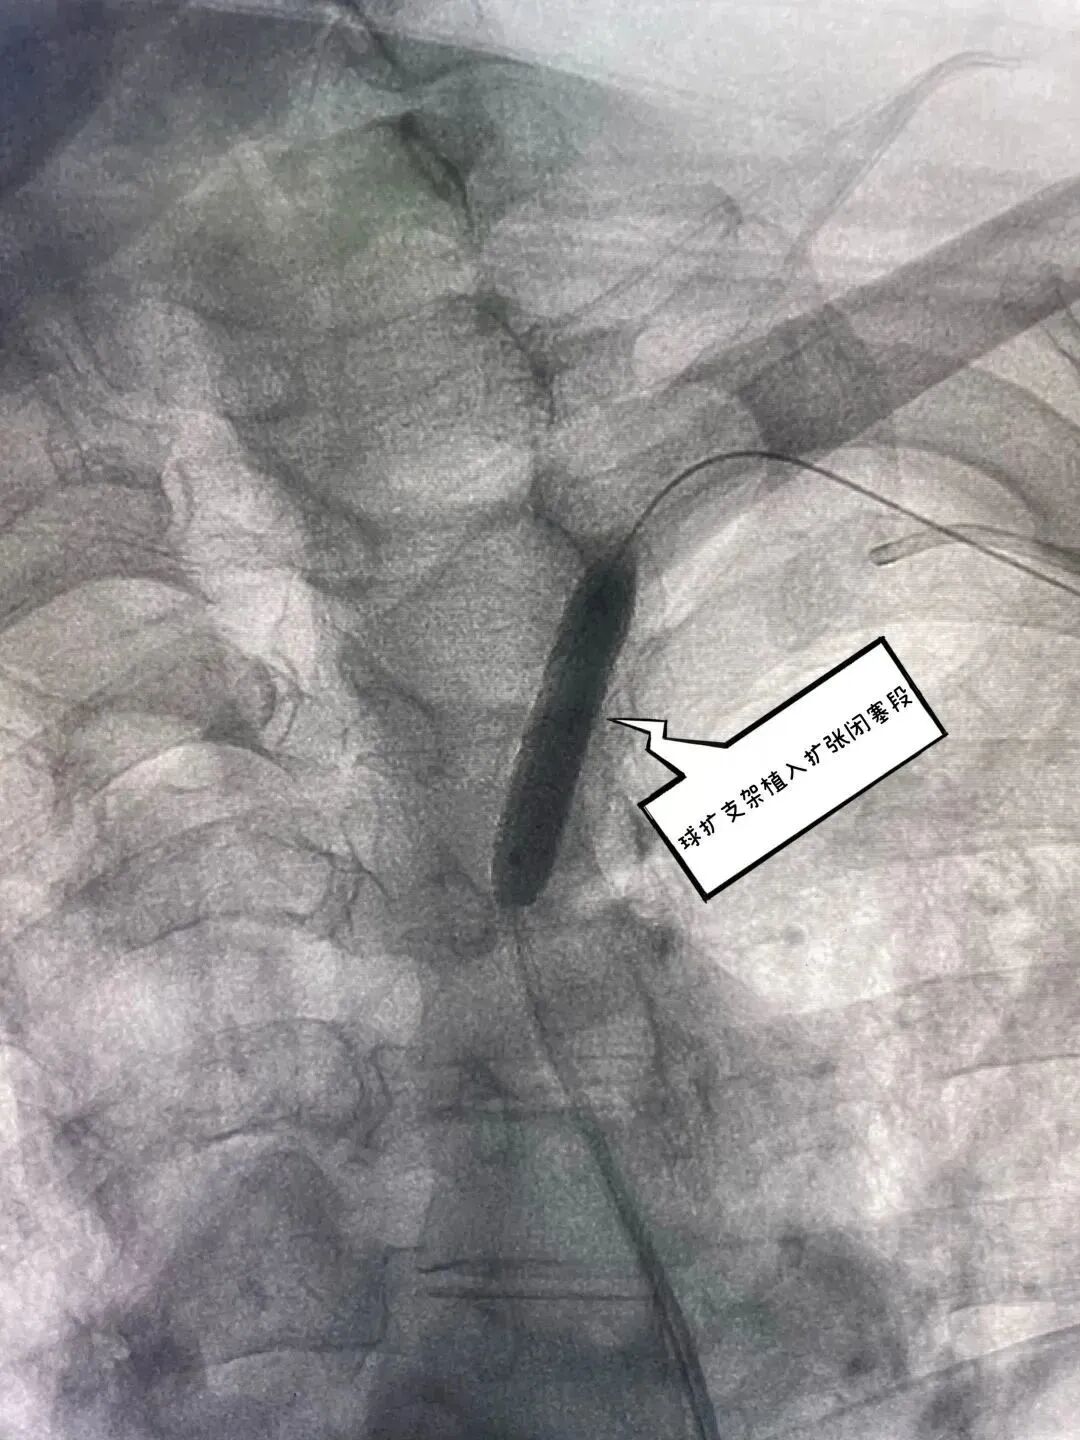

球扩支架植入闭塞段                        复查造影闭塞血管再通,成形良好,前向血流恢复